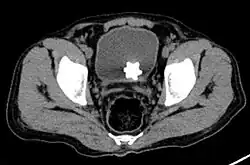

El diagnóstico de cálculos vesicales incluye análisis de orina, ecografía, radiografías o cistoscopia (que consiste en insertar una pequeña cámara delgada en la uretra y observar la vejiga). El pielograma intravenoso también se puede utilizar para evaluar la presencia de cálculos renales. Esta prueba implica la inyección de un agente de radiocontraste que se introduce en el sistema urinario. Luego se obtienen imágenes de rayos X cada pocos minutos para determinar si hay alguna obstrucción en el contraste mientras se excreta en la vejiga. Hoy en día, el pielograma intravenoso ha sido reemplazado en muchos centros de salud por la tomografía computarizada. Las tomografías computarizadas son más sensibles y pueden identificar cálculos muy pequeños que son detectados con otras pruebas.